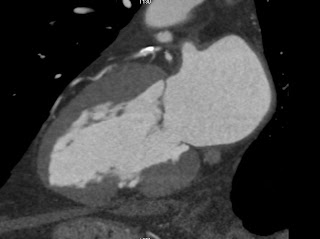

Le scanner met tout le monde d’accord, il s’agit d’un pseudo pseudo-anévrisme avec de la paroi, qui est le siège d’une transformation lipomateuse, visible en noir sur le scanner (graisse). Il n’y a donc pas d’indication chirurgicale.